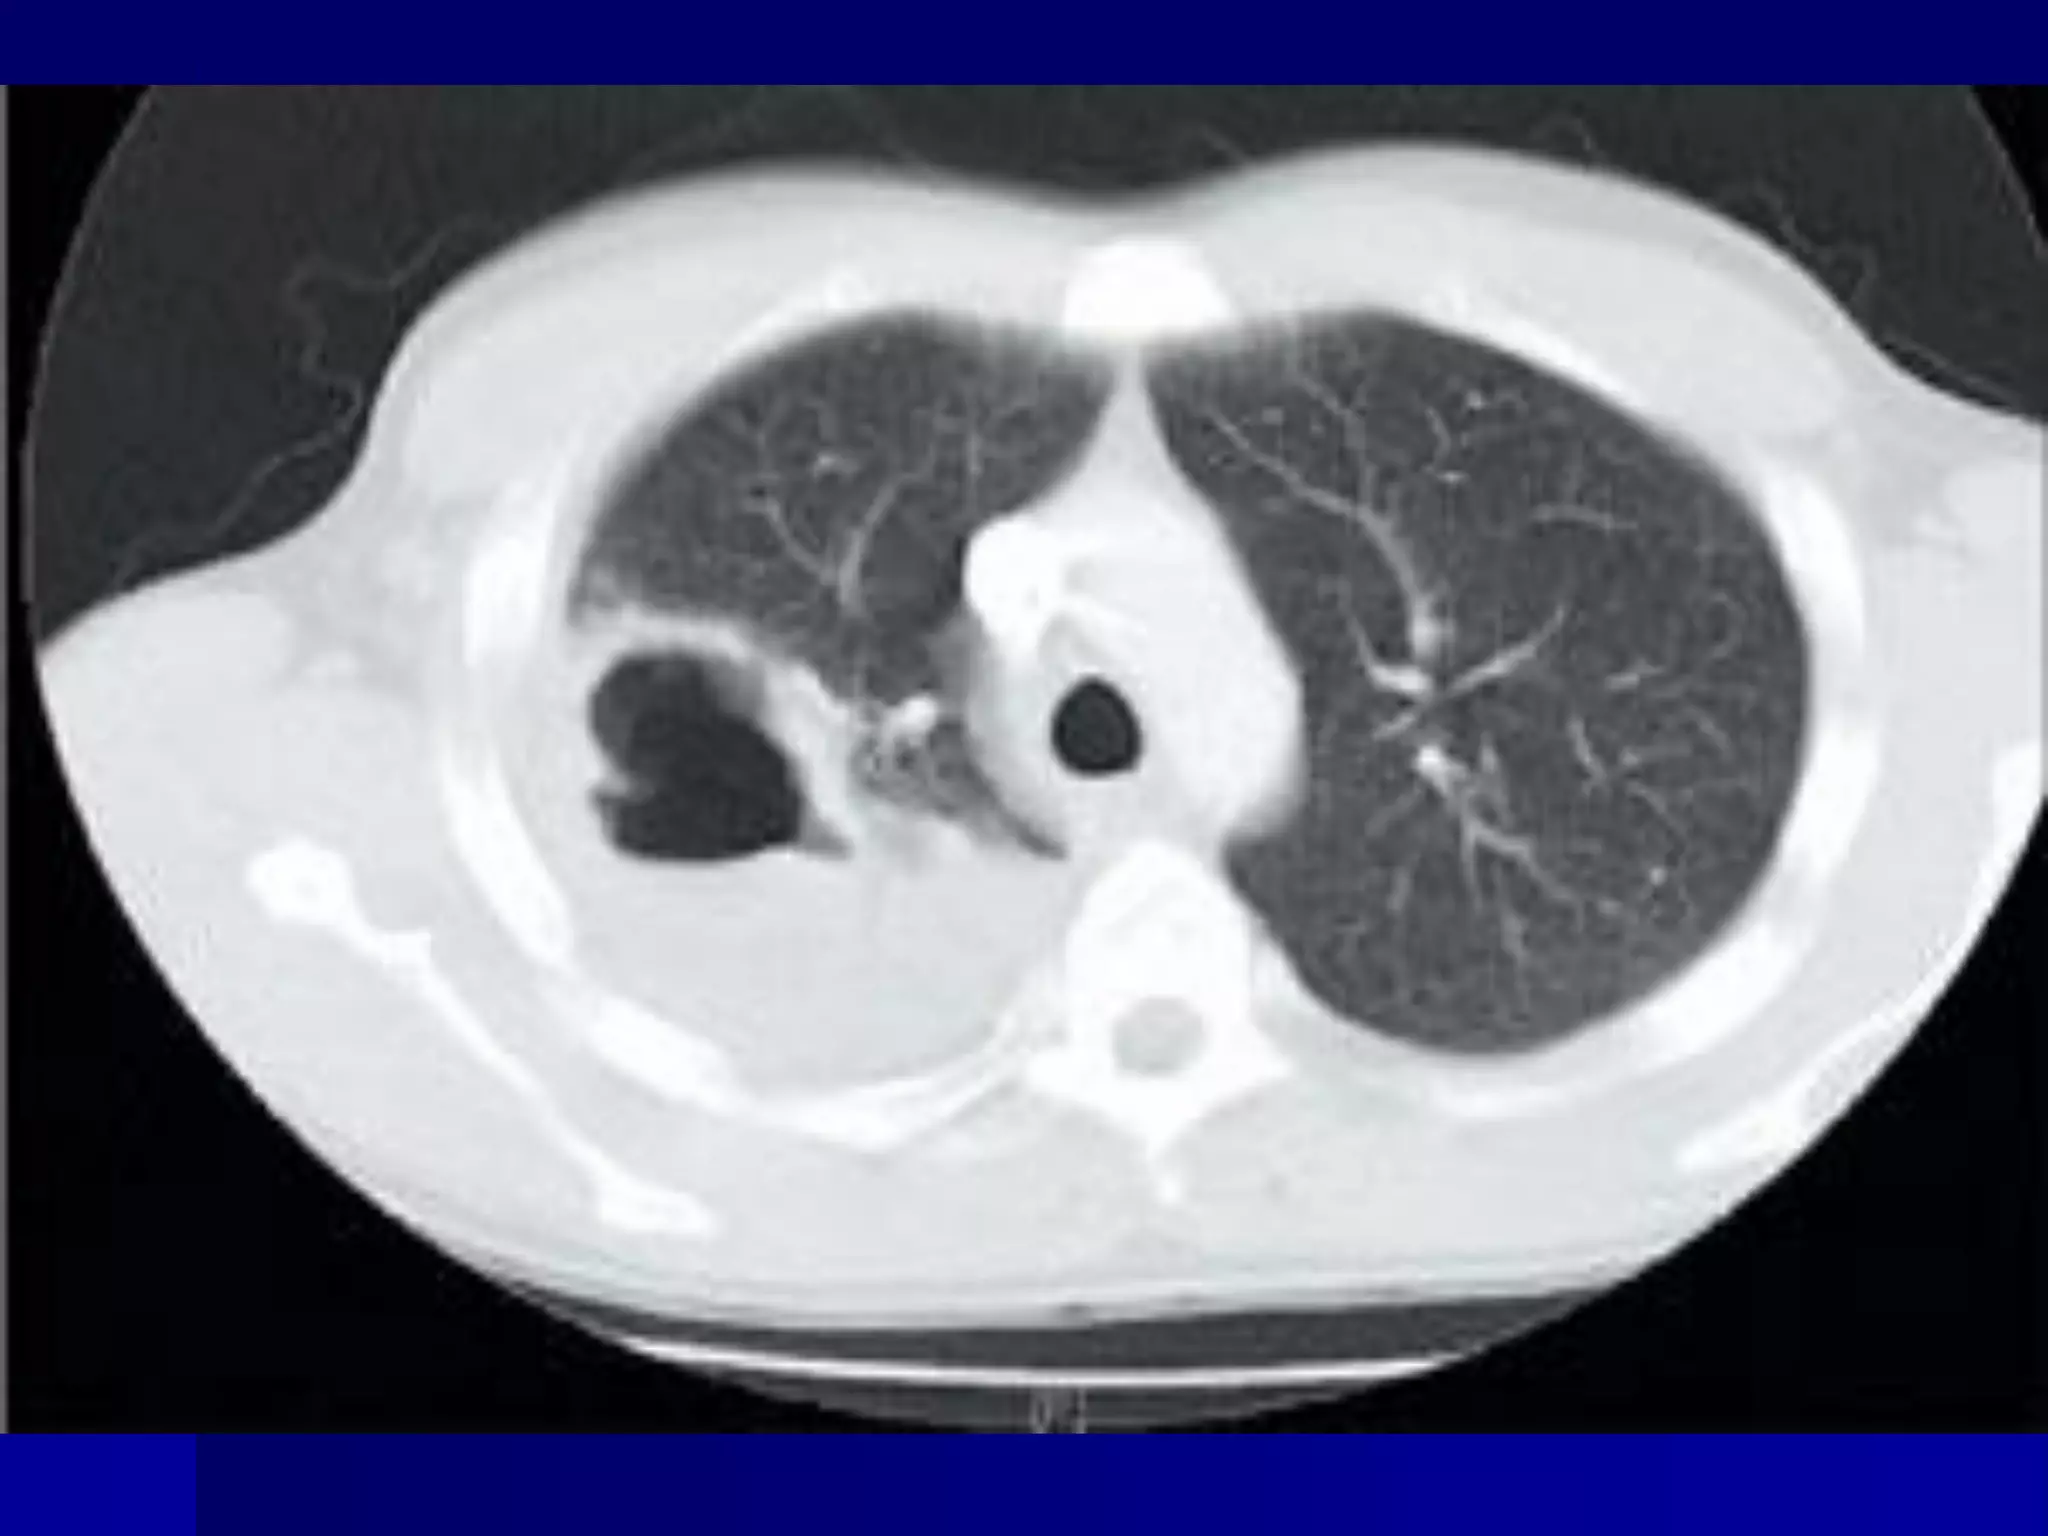

CT Scan and MRI Scan in the

diagnosis of TB

􀂄 The advent of CT and MRI imaging in

the last two

decades has redefined the approach in

analysis of

various diseases including TB.*

􀂄 CT and MRI have shown several

advantages over

conventional radiology in early diagnosis

and follow-up

of TB in different parts of the body.

*Buxi TBS Indian J Pediatr 2002;69:965-972

Pulmonary TB :

Lobar Pneumonia

􀂄

CT is superior than plain CXR in picking

up the

consolidation, atelectasis and the hilar LN

thereby

making the diagnosis easy.

􀂄 MRI reveals some of these changes,

however, CT is

the diagnostic modality of choice in such

cases.

Bronchopneumonia

On CT it is usually B/L and widespread,

not always

symmetrical involvement of lungs.

Hilar and Mediastinal

Lymphadenopathy

CT and MRI depict the hilar and

mediastinal LN

equally well.

􀂄 Calcification in the nodes is however

better seen on

CT.

􀂄 Necrosis is seen as focal areas of low

attenuation on

a CECT.

􀂄 On MRI focal necrosis is seen as areas

of increased

signal intensity on T2W images.